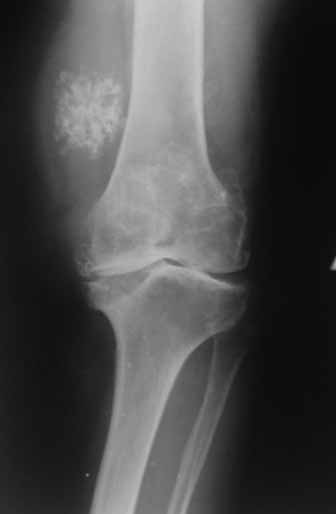

Пациентка 72 лет.Не обследовалась и не лечилась.

Работала поварихой до последнего времени. обратилась за медпомощью впервые. ходит без

дополнительной опоры. Основные жалобы на ограничение движений и боли в правом коленном

суставе. Финансовые возможности ограничены. Чем можно помочь? Артродез? Протезирование?